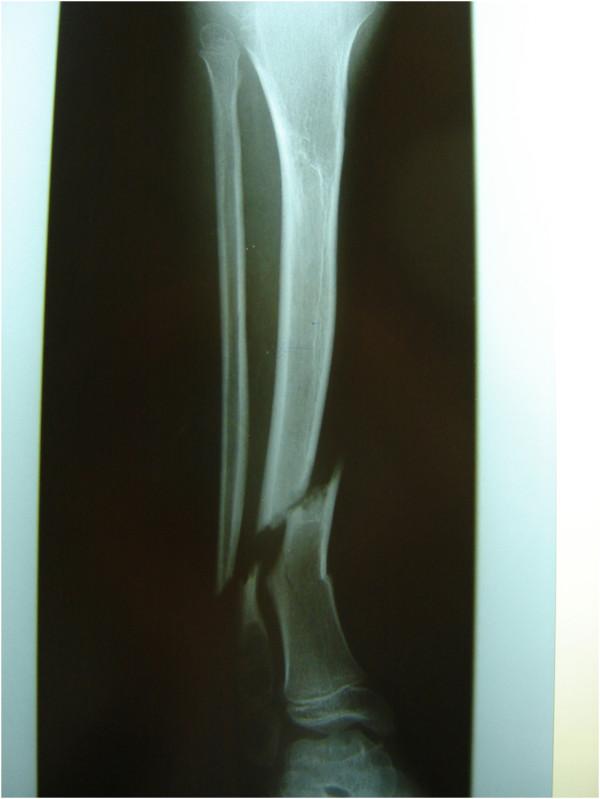

We report a nine-year-old Caucasian girl who had hereditary motor and sensory neuropathy type I and who was admitted with a grade I open tibia fracture after a fall from a small height. Plain radiographs showed a dislocated tibia and fibula fracture. An open reduction with internal fixation with a compression plate osteosynthesis was performed, and soft tissue debridement combined with an external fixateur was undertaken. Three months later, she was re-admitted with localized swelling and signs of a local soft tissue infection in the middle of her tibia. Plain radiographs showed a non-union of the tibia fracture, and microbiological analysis confirmed a wound infection with cefuroxime-sensitive Staphylococcus aureus. Because of the non-union, the osteosynthesis was replaced with an Ilizarov external fixateur, and appropriate antibiotic therapy was initiated. Four months after the initial accident, the fracture was consolidated and we removed the external fixateur.

我们报告一名9岁的白种女孩,她患有I型遗传性运动和感觉神经病变,因从低处跌落导致I级开放性胫骨骨折入院。X线平片显示胫骨和腓骨骨折脱位。进行了切开复位并用加压钢板内固定,同时进行了软组织清创并结合外固定架。三个月后,她再次入院,胫骨中部出现局部肿胀和局部软组织感染迹象。X线平片显示胫骨骨折不愈合,微生物分析证实伤口感染了对头孢呋辛敏感的金黄色葡萄球菌。由于骨折不愈合,将内固定换成了伊里扎洛夫外固定架,并开始了适当的抗生素治疗。初次事故四个月后,骨折愈合,我们拆除了外固定架。